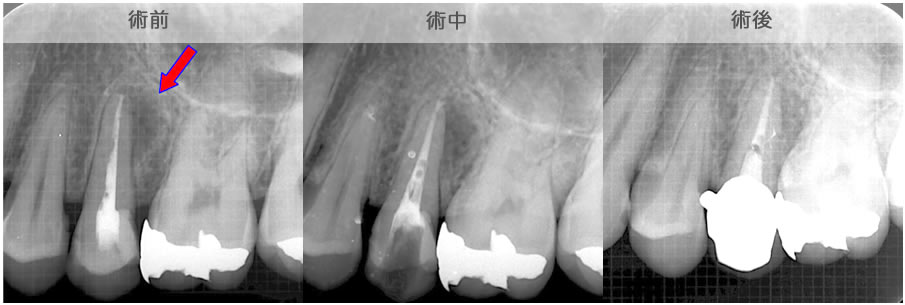

CT画像を見ると根管が2本あることが分かりました。(レントゲンだけでは分かりませんでした。)

| 治療説明 | 右下第2小臼歯、他院で根管治療した後に頬側根尖部から排膿があます。X線CT画像では、根管が2本あり、そのうち舌側が根管充填されていませんでした。顕微鏡下で2根管とも根管充填処置を行い、4ヶ月で、X線透過像は消失しました。 |

|---|---|

| 治療期間 | 6〜24ヶ月 |

| 治療費用 | 150,000〜300,000円 |

| 治療に伴うリスク | 根管内からの治療で根尖病巣が治らない場合は、外科的に根尖病巣を除去する必要があります。 再根管治療を繰り返す場合、歯根の厚みが薄くなり、歯根破折のリスクが高まります。 |